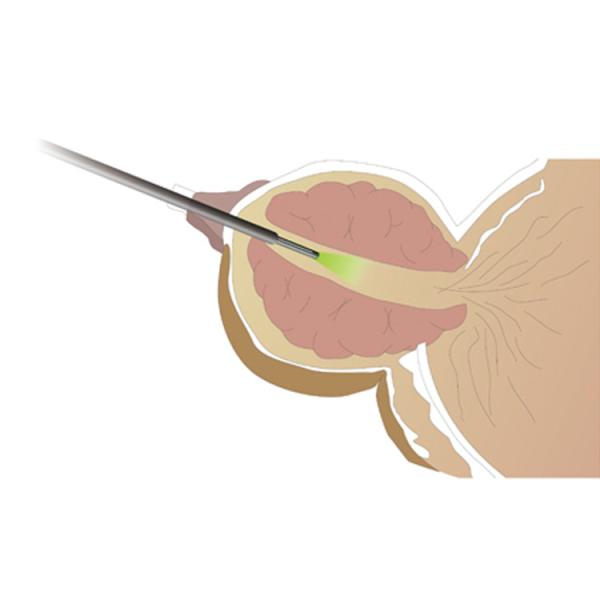

AURORA Laboratory Medical Equipment High Power Green Laser BPH Surgery System Images |